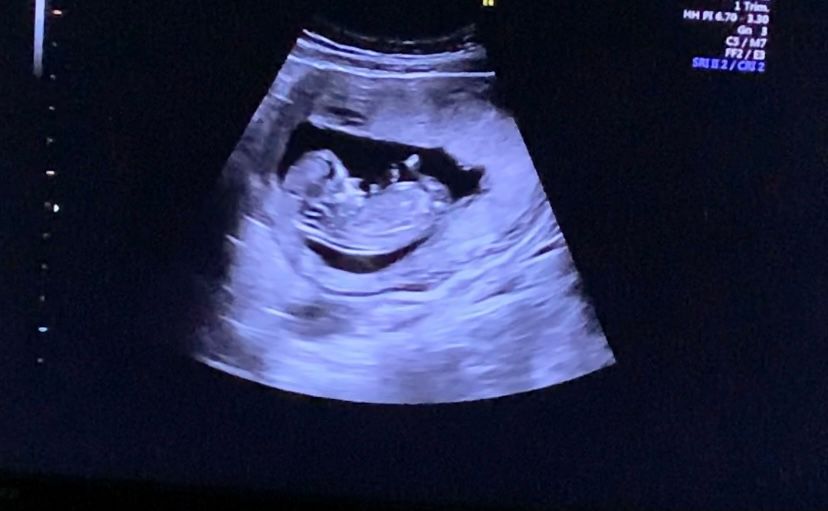

Девочки , мальчик или девочка?

12 Недель , сказали половой бугорок кверху , посмотрите пожалуйста :)

Не знаю, где тут что кверху, а вот то, что к нам попкой больше, это да. В общем, не видно

У меня был вверх в 13 недель. Говорили 90% мальчик. В итоге девочка) похожи наши бугорки

Мне тоже предположили мальчика☺️ Остаётся ждать второго узи. С мальчиками реже ошибаются.

😂😂😂 мне кажется, на последнем фото в уголке фигура из 3х пальцев . Вообще кверху парень, а девочка- он параллелен тельцу. Но это же опять из теории и прочитанного.